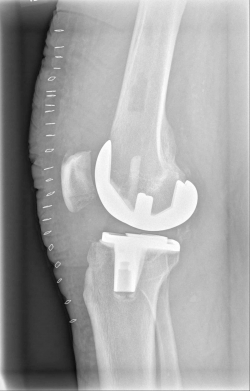

Example X-ray images before and after implantation of a Persona knee prosthesis with robot.

b) nach Implantation der Knie-Totalendoprothese angefertigte Röntgenaufnahmen |